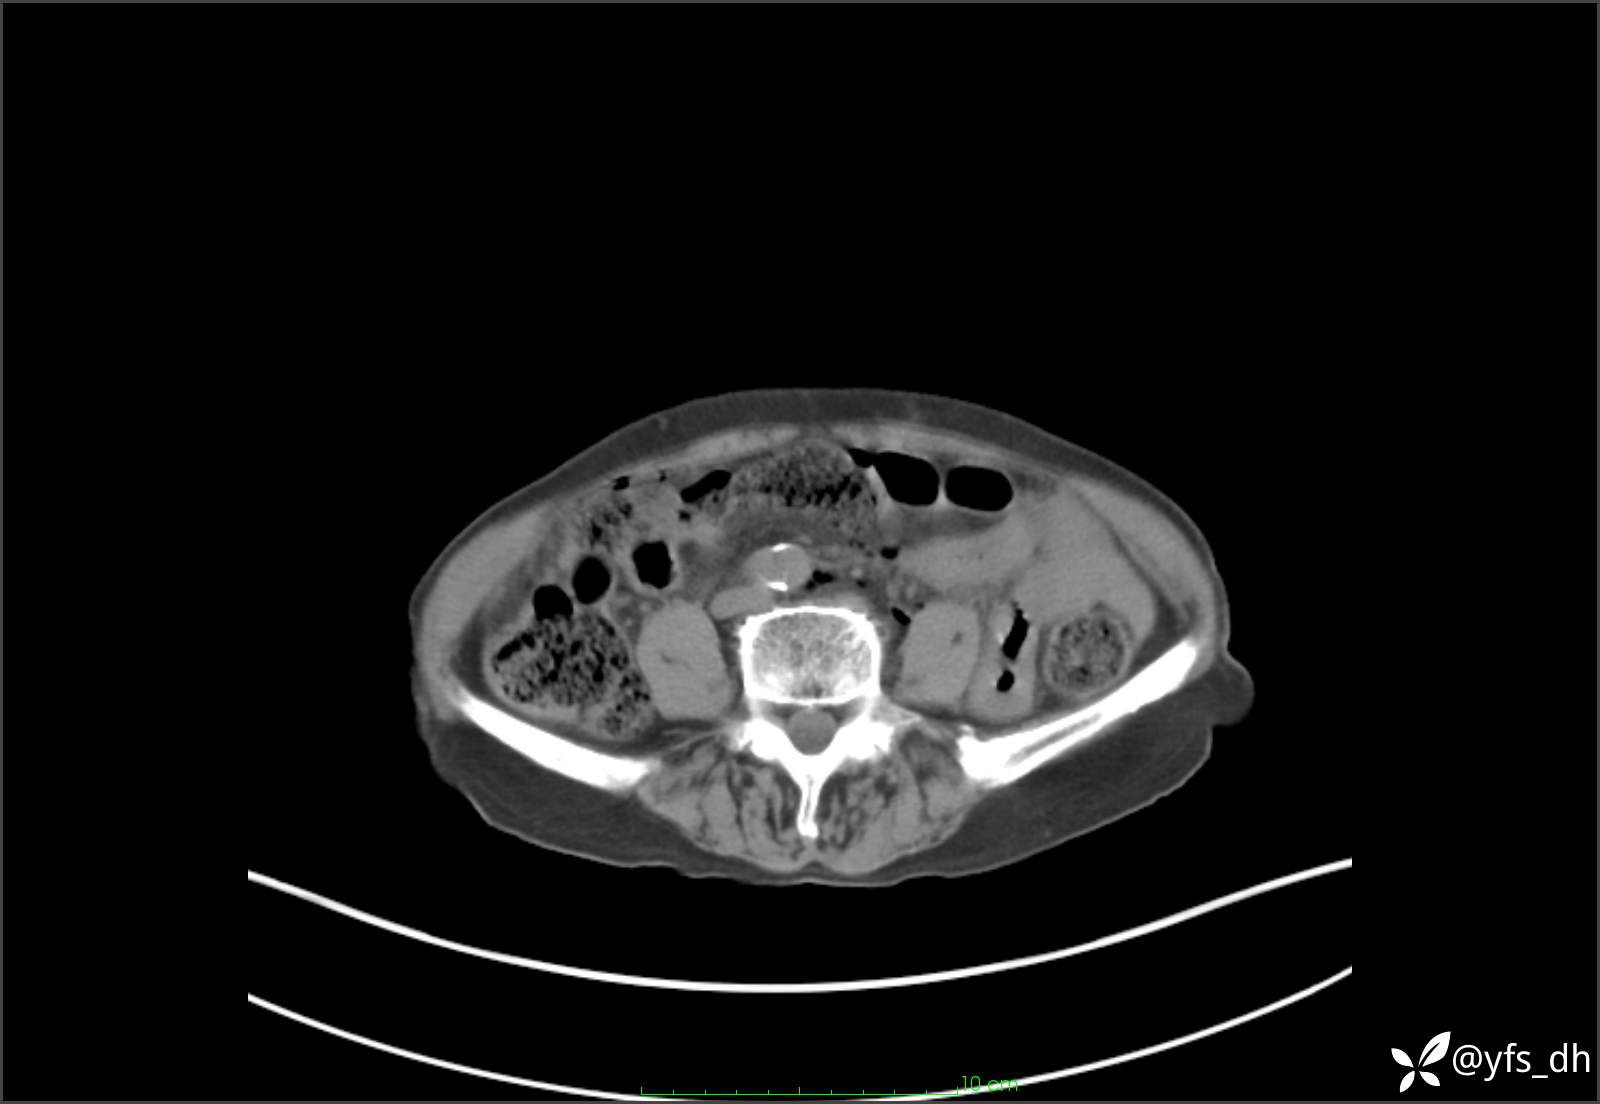

1.简要病史:患者4天前突发上腹部疼痛不适,但可以忍受。3小时前饭后突然加重,不能忍受后就诊。

2.简要手术记录:术中见腹盆腔大量肠液及粪便,乙状结肠中下段见一约3cm的破口。